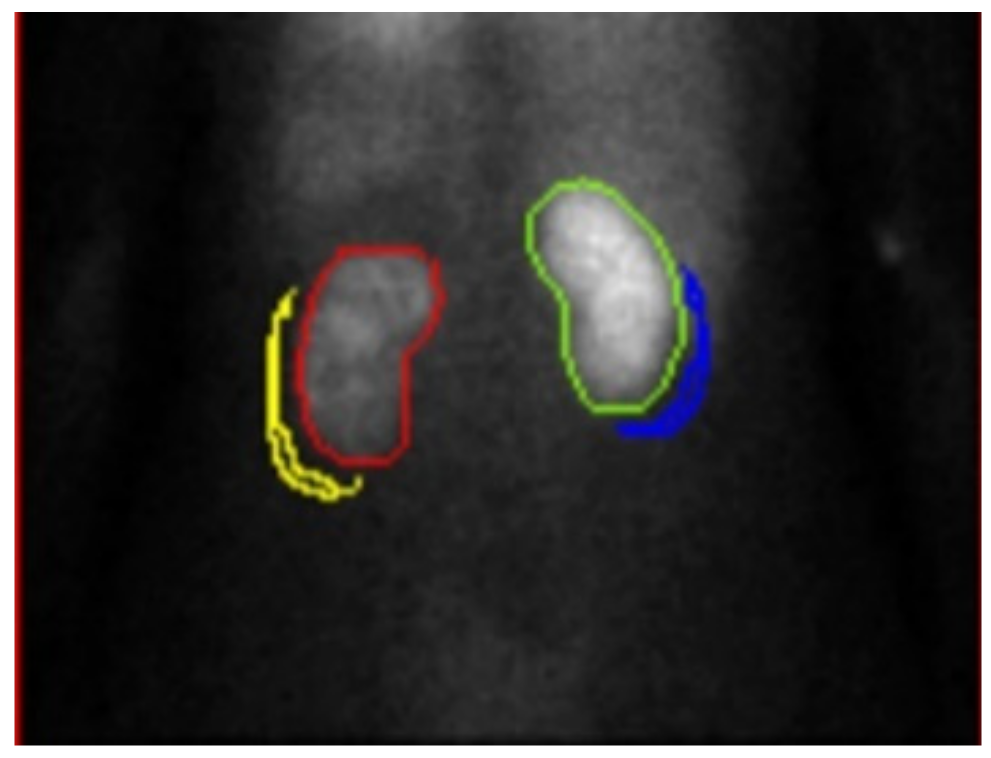

2.2. Renal Dynamic Image

2.3. Assessment of Renal Depth by Tonnesen’ s Formula

2.4. Assessment of Renal Depth by Itoh K’s Formula

2.5. Assessment of Renal Depth by Taylor’s Formula

2.6. Assessment of Renal Depth by CT